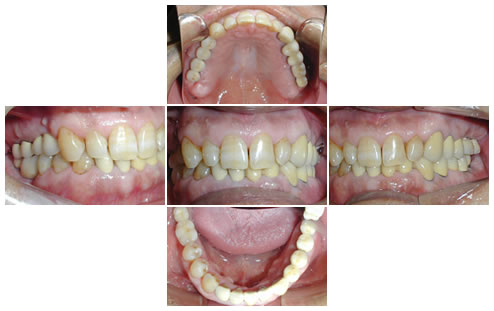

インプラントの治療例-1-

50代の男性の患者様です。奥歯の咬み合わせがなく、物を咬んで食べられないので歯を入れたいということで来院されました。

ところが「入れ歯はイヤだ」ということでしたので、患者様の希望にそえるように治療計画を話し合った結果、インプラント治療をおこなうことにしました。

写真の上が、治療前の口腔内写真で、下がレントゲンです。

12本のインプラントを植立し、全額補綴処置をおこないました。臼歯部の咬合高径(咬み合わせの高さ)を上げて安定させました。

治療終了後に患者様は、「奥歯で咬めるってこんなに良いとは思わなかった」と喜んでおられました。